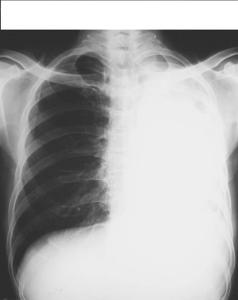

单侧肺气肿的狭义定义指因先天性肺组织及肺循环发育异常,使患肺能较正常肺组织透过更多X线的肺部疾病。也有人将阻塞性或代偿性肺气肿、肺大疱,气性肺囊肿等称为透明肺,此可以理解为广义的范畴。[1]